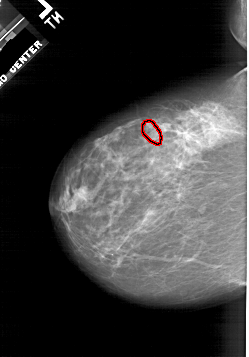

A_1941_1.LEFT_MLO

LEFT_MLO LINES 5986 PIXELS_PER_LINE 4276 BITS_PER_PIXEL 12 RESOLUTION 43.5 OVERLAY

FILE: A_1941_1.LEFT_MLO.OVERLAY

TOTAL_ABNORMALITIES 1

ABNORMALITY 1

LESION_TYPE CALCIFICATION TYPE PLEOMORPHIC DISTRIBUTION CLUSTERED

ASSESSMENT 4

SUBTLETY 2

PATHOLOGY BENIGN

TOTAL_OUTLINES 1

BOUNDARY